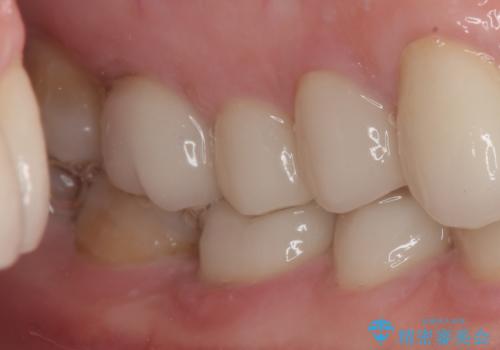

口を開けたときに見える範囲をオールセラミッククラウンとし、とても自然な口元に仕上げることができました。